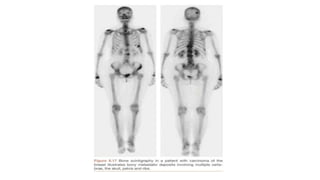

Radionuclide scan

- A radioactive element (radionuclide) is administered as a radio

pharmaceutical agent and a detector ( gamma camera ) is used to record and

localise the emission ( gamma ray ) and thus form an image

- Agents : technetium,gallium,thallium,iodine

- These are usually labelled for organ specificity

Radionuclide scan - Aradioactive element (radionuclide) is administered as a radio pharmaceutical agent and a detector ( gamma camera ) is used to record and localise the emission ( gamma ray ) and thus form an image - Agents : technetium,gallium,thallium,iodine - These are usually labelled for organ specificity